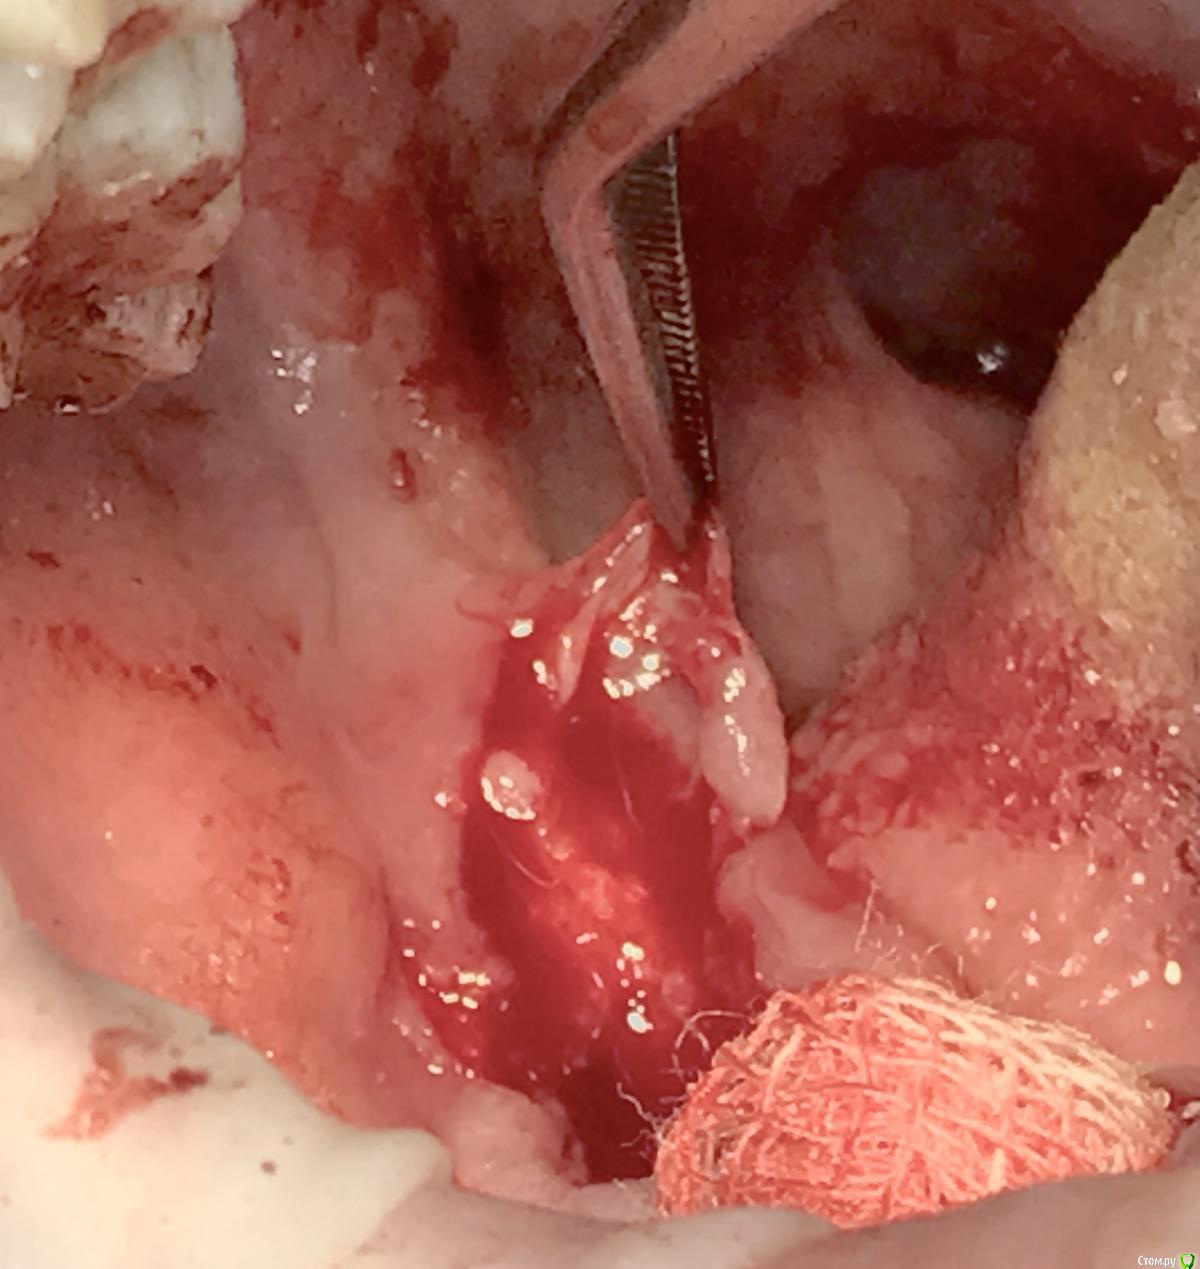

Irouil Опубликовано 23 апреля, 2017 Поделиться Опубликовано 23 апреля, 2017 Блин, как полезно иногда лля форума фоткать. В жизни бы не увидел, что шов оставил. Тут типичная "полуретенция" была - самый мерзкий вариант, имхо. Легкий дистальный наклон, передний край ветви "козырьком" над коронкой, медиально прорезан на пол коронки. Единственный напряг - вестибюлярно складка, но там просто поднадкостнично гематома, я не стал трогать. Ссылка на комментарий

колесников Опубликовано 6 мая, 2017 Автор Поделиться Опубликовано 6 мая, 2017 Воспользовался случаем попрактиковаться в выделении язычного лоскута. Разрез поверхностный,далее расщепление и выделение.По поводу лоскута без графта. Дважды пришлось так поступить. В первом случае расхождение краев за 7кой с образованием щели и застревание пищи. Во втором случае мезиально все герметично,дистально (?) щель,при зондировании -пусто. Итого: лоскут без графта-так себе вариант. Ссылка на комментарий